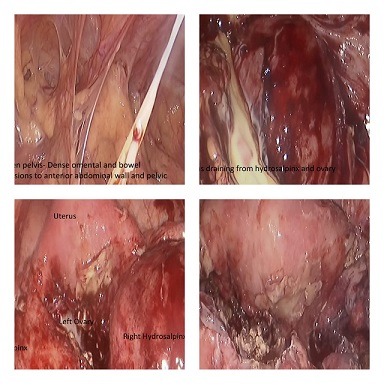

MINIMAL ACCESS SURGERY IN A FROZEN PELVIS. 28 year old female presented with complaints of lower abdominal pain, fever on and off, weight loss and infertility. Due to worsening pain, CT scan was performed which revealed bilateral hydrosalpinx and ovarian cyst, suggestive of ? TB or? Chronic PID. Laparoscopy was planned with consent for bilateral salpingectomy and ovarian cystectomy. Laparoscopy revealed a frozen pelvis with dense omental and bowel adhesions to anterior abdominal wall, uterus, both hydrosalpinx and ovaries. Systematic adhesiolysis was done to visualise pelvic structures. Dense bowel adhesions were removed with difficulty with sharp and blunt dissection.Large amount of frank pus was drained from both Hydrosalpinx and left ovary. Bilateral salpingectomy and ovarian pus drainage was done with copious peritoneal lavage.